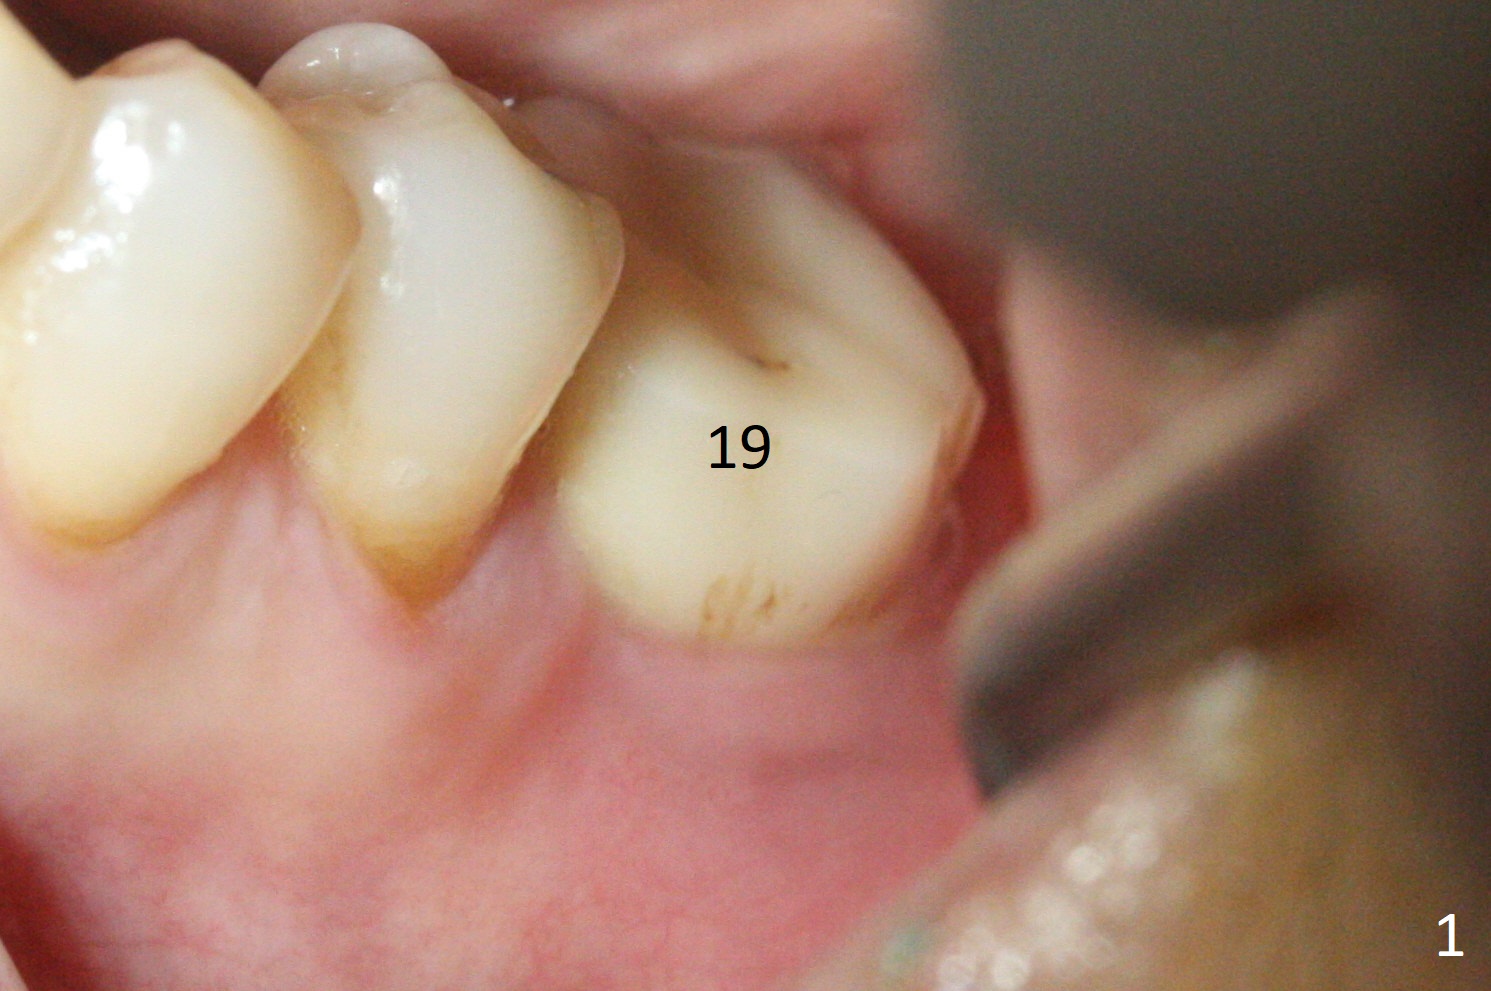

When the patient returns for treatment, the implant at #19 is mobile with tenderness (without purulence, Fig.1). She finally agrees to have CT taken (Fig.2,3 (coronal section (L: lingual))). The implant is removed after several carpules of cocktail anesthetics for infiltration and one carpule for block. Osteotomy is initiated in the mesial slope of the defect (Fig.2,4). The advantage of immediate implant re-placement is wide bone at the intended area (Fig.3). After change in trajectory (compare Fig.4 (4x11 mm dummy implant) and Fig.5), a 4.5x9 mm IBS implant is placed with insertion torque of 50 Ncm (Fig.5); with Osteogen plug placed in the distal defect, allograft (*) is placed immediately distal to the implant. With the longest cuff available (4 mm), the margin of the abutment (4.5x4(4) mm) is equi-crestal (>). When the 9 mm long implant is placed deep, the coronal threads of the implant are distally exposed (Fig.6 between arrowheads) less than those of the 11 mm one placed superficial (Fig.2). Intraoperative socket hemorrhage is controlled by packing gauze saturated with Epinephrine 1:50,000. The patient chooses not to take Medrol Dose Pack for postoperative edema. She removes periodontal dressing herself prematurely. The socket wound dehiscence is noted the first postop visit (7th day). Fig.7 is taken 9 days postop before re-suturing. The patient insists on removing the implant with dull pain. Three months 10 days postop, she returns with loss of the abutment and a fistula (Fig.8). In fact there is bone formation distal to the implant. Torque wrench has to used to remove the implant.